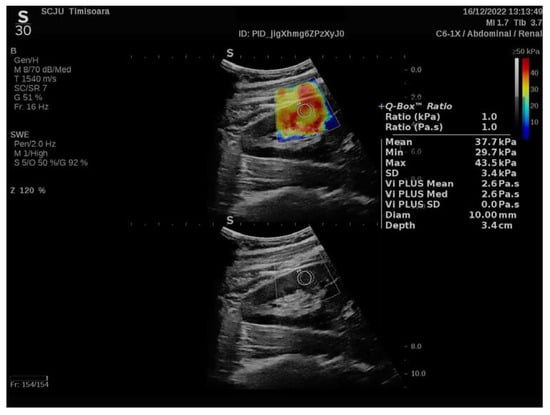

2.2. Elastography